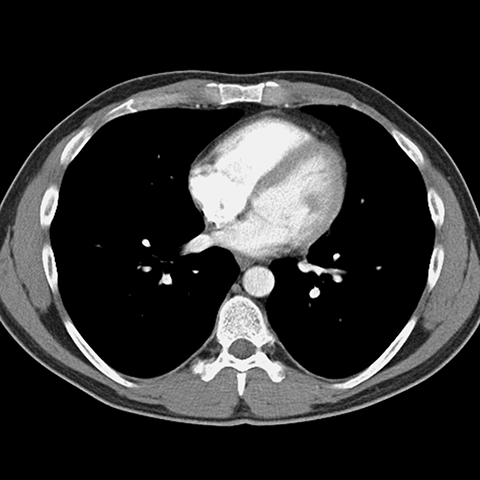

Normal Contrast-Enhanced CT (Mediastinal Window) [8 of 8]